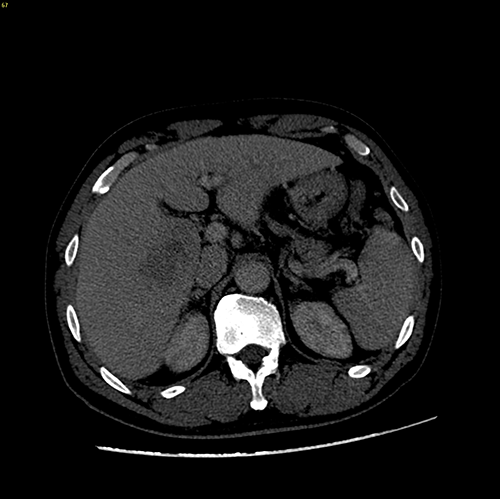

右肝癌、门静脉癌栓----右半肝切除,门静脉癌栓取出术

手术规划--右半肝切除,门静脉取癌栓